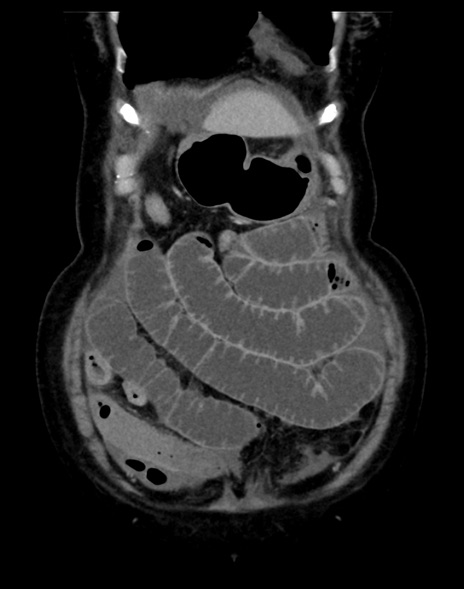

(横断像)1日半後